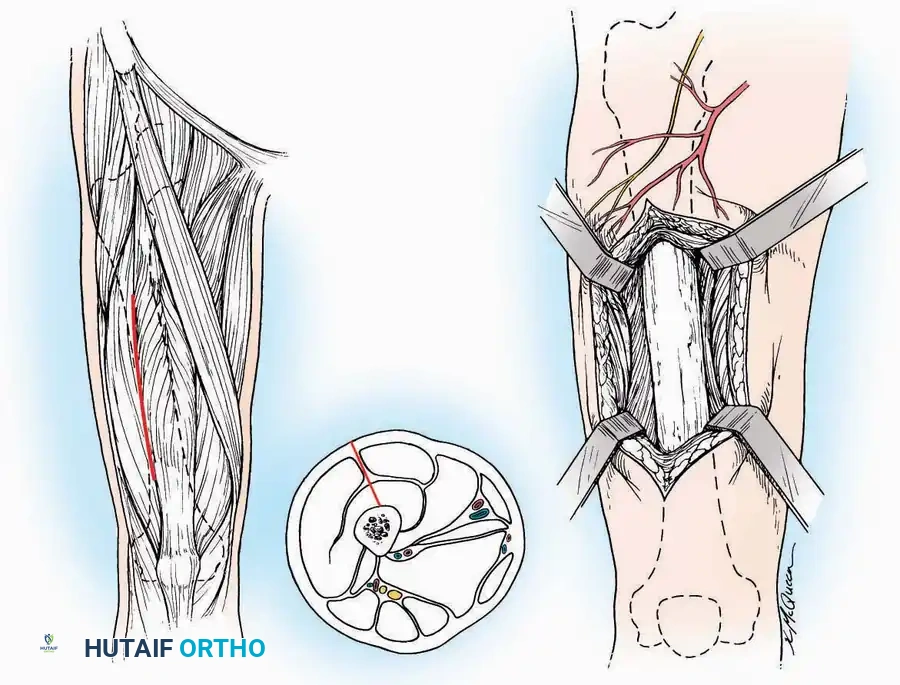

Anterolateral Approach

The anterolateral approach is widely considered the "universal incision" for the foot and ankle. It provides unparalleled access to the ankle joint, the talus, and the majority of the tarsal articulations, while safely avoiding the major anterior neurovascular bundle. The only tarsal joints inaccessible via this route are the naviculocuneiform joints (specifically the medial and intermediate).

Indications: Total talectomy, triple arthrodesis, ankle arthrodesis, and open reduction of complex talar neck fractures.

Surgical Technique:

* Incision: Begin over the anterolateral aspect of the leg, medial to the fibula and 5 cm proximal to the ankle joint line. Carry it distally over the joint, crossing the anterolateral aspect of the talar body and the calcaneocuboid joint, terminating at the base of the fourth metatarsal.

* Superficial Dissection: Incise the superficial fascia and the superior and inferior extensor retinacula down to the periosteum of the tibia and the ankle joint capsule.

* Vascular Ligation: This trajectory usually requires the identification and ligation of the anterolateral malleolar and lateral tarsal arteries.

* Nerve Protection: Retract the skin edges carefully. Identify and protect the intermediate dorsal cutaneous branches of the superficial peroneal nerve (SPN), which frequently cross the distal aspect of this incision.

* Muscle Management: Identify the origin of the extensor digitorum brevis (EDB) muscle on the lateral calcaneus. Divide it in the direction of its fibers, or detach its origin entirely and reflect it distally to expose the subtalar and calcaneocuboid joints.

* Deep Exposure: Retract the extensor digitorum longus (EDL) tendons, the dorsalis pedis artery, and the deep peroneal nerve (DPN) medially. Incise the anterior ankle capsule to expose the tibiotalar joint.

* Tarsal Exposure: Expose the talonavicular joint by dissecting deep to the extensor tendons and incising its capsule transversely. Continue laterally through the capsule of the calcaneocuboid joint. By excising the fat pad within the sinus tarsi (lateral and inferior to the talar neck), the posterior facet of the subtalar joint is brought into direct view.